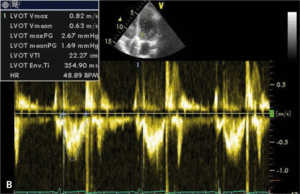

Rycina. Pomiar efektywnego pola ujścia protezy zastawkowej u chorej z wszczepioną sztuczną zastawką aortalną St Jude Medical 21A.

Ocenę funkcji wszczepionej zastawki umożliwia echokardiografia (ryc. 1). Ocena protezy zastawkowej wszczepionej w pozycję aortalną powinna uwzględniać analizę maksymalnej prędkości przepływu przez zastawkę (VmaxAo), średniego przezzastawkowego gradientu ciśnień (PmeanAo), całki prędkości przepływu w czasie przez zastawkę aortalną (VTIAo) i w drodze odpływu lewej komory (VTILVOT), indeksu prędkości przepływu proksymalnie do zastawki i prędkości na poziomie zastawki (DVIAo), efektywnego pola ujścia protezy zastawkowej (EOAAo), a także czasu akceleracji przepływu przez protezę zastawkową (ATAo) (tab. 1).

Liczne obserwacje i badania pozwoliły na opracowanie metody stosowanej do oceny wielkości wszczepianej zastawki w celu przeciwdziałania zjawisku niedopasowania [8-10]. Do ilościowej oceny stopnia niedopasowania zastawki aortalnej możemy posłużyć się tzw. indeksem efektywnego pola ujścia protezy zastawkowej aortalnej (EOAIAo), obliczanym z przekształconego wzoru ciągłości przepływu przez zastawkę aortalną:

W którym EOAAo oznacza efektywne pole ujścia protezy zastawkowej aortalnej, LVOTd – wymiar drogi odpływu lewej komory, VTILVOT – całkę prędkości przepływu w czasie w drodze odpływu lewej komory, a VTIAo – całkę prędkości przepływu w czasie przez zastawkę aortalną.